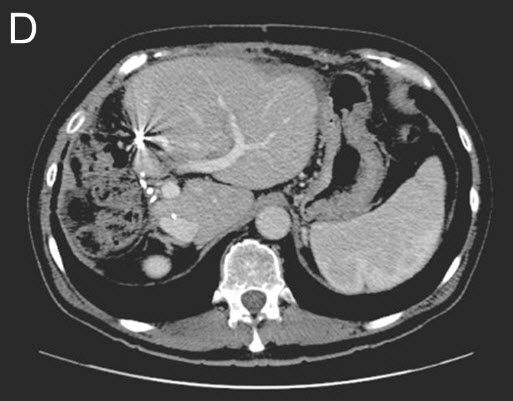

![]() |

(D) Stage II - Second Surgery: The right liver and tumors are removed. CT-Scan shows additional growth (hypertrophy) of the remaining liver remnant. |